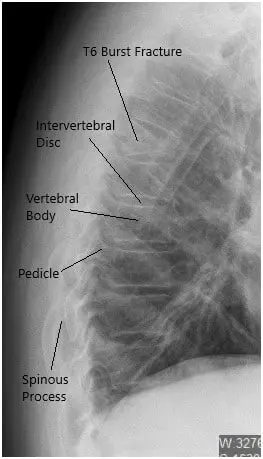

She presented to the emergency room at the Hospital in excruciating amounts of pain. An imaging workup revealed a burst fracture of the T6 vertebral body with more than 50% loss of height and acute angulation at that level, which worsened with flexion and extension.

Preoperative X-ray of the Thoracolumbar Spine in Lateral View.

CT revealed moderate acute wedge compression fracture associated with the T6 vertebral body. The posterior cortex of the T6 vertebral body mildly impresses upon the anterior margin of the thoracic dural sac. Minimal hematoma is situated between the T6 vertebral body and the surrounding pleura.